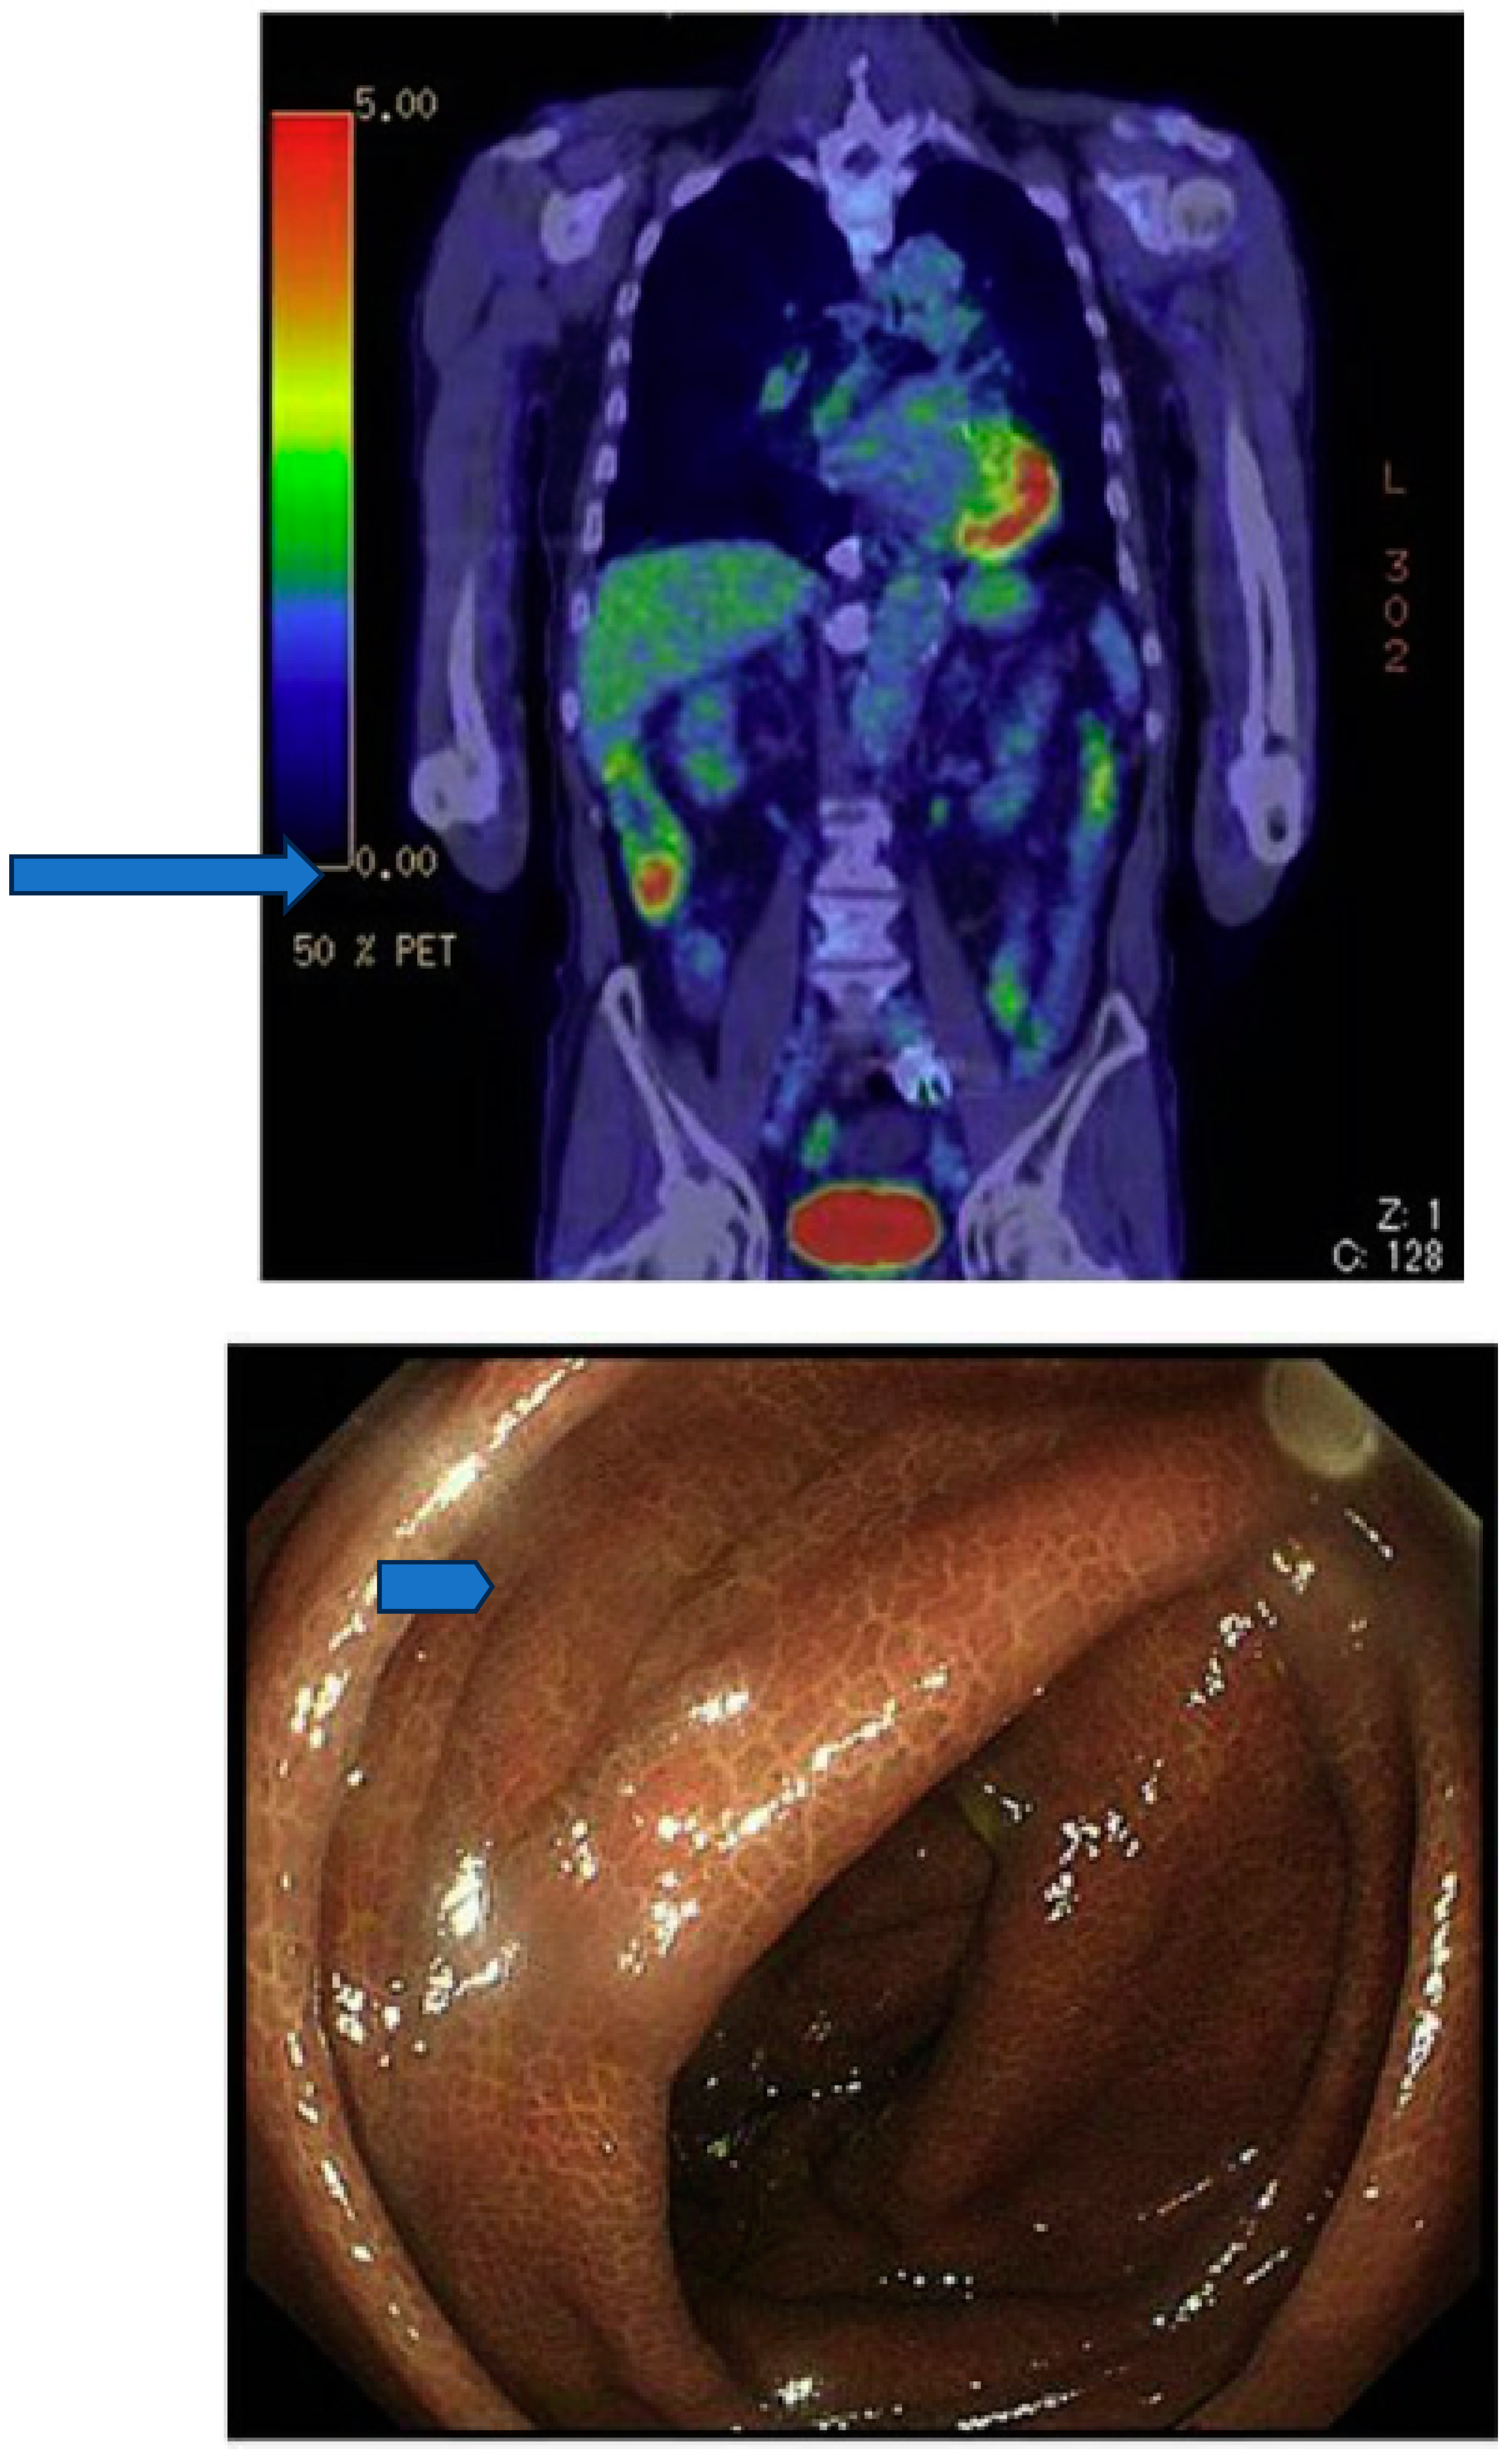

Morita and coworkers by using positron emission tomography (PET)-MRI, recently found that the maximum standardized uptake value (SUVmax) of F18-FDG in the intestine (jejunum,ileum and right or left hemicolon) of metformin treated diabetics was higher than that of the control group.More importantly the study permitted to differentiate the SUVmax of the intestinal wall from that of the intestinal lumen.The SUVmax of the intraluminal space in metformin-treated diabetics was greater than that of controls (Figure 2).On the contrary the SUVmax of the intestinal wall was similar in both groups (131).An increased accumulation of the injected tracer seems to be appreciable (Figure 3) also in the liver of metformin-treated diabetics up to 48 hours after interruption of the oral uptake of the drug (132,133).

Accumulation of F18-FDG in the large intestine (Figure 4) has been found also in persons who regularly use laxatives (136-137).SUVmax can even reach levels,which simulate those of colorectal neoplasms (Figure 5) in patients with chronic constipation (138).

Figure 3. PET-scan performed in diabetics at different time after interruption of metformin therapy.In patient 4 interruption time was shorter than 48 hours and shows strong accumulation of the tracer in the colon. From Schreuder N et al.(133).